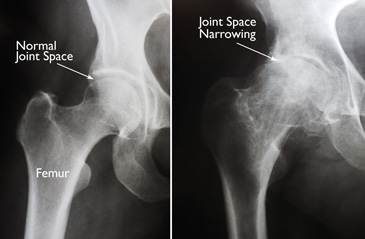

(Left) In this x-ray of a normal hip, the space between the ball and socket indicates healthy cartilage. (Right) This x-ray of an arthritic hip shows severe loss of joint space.